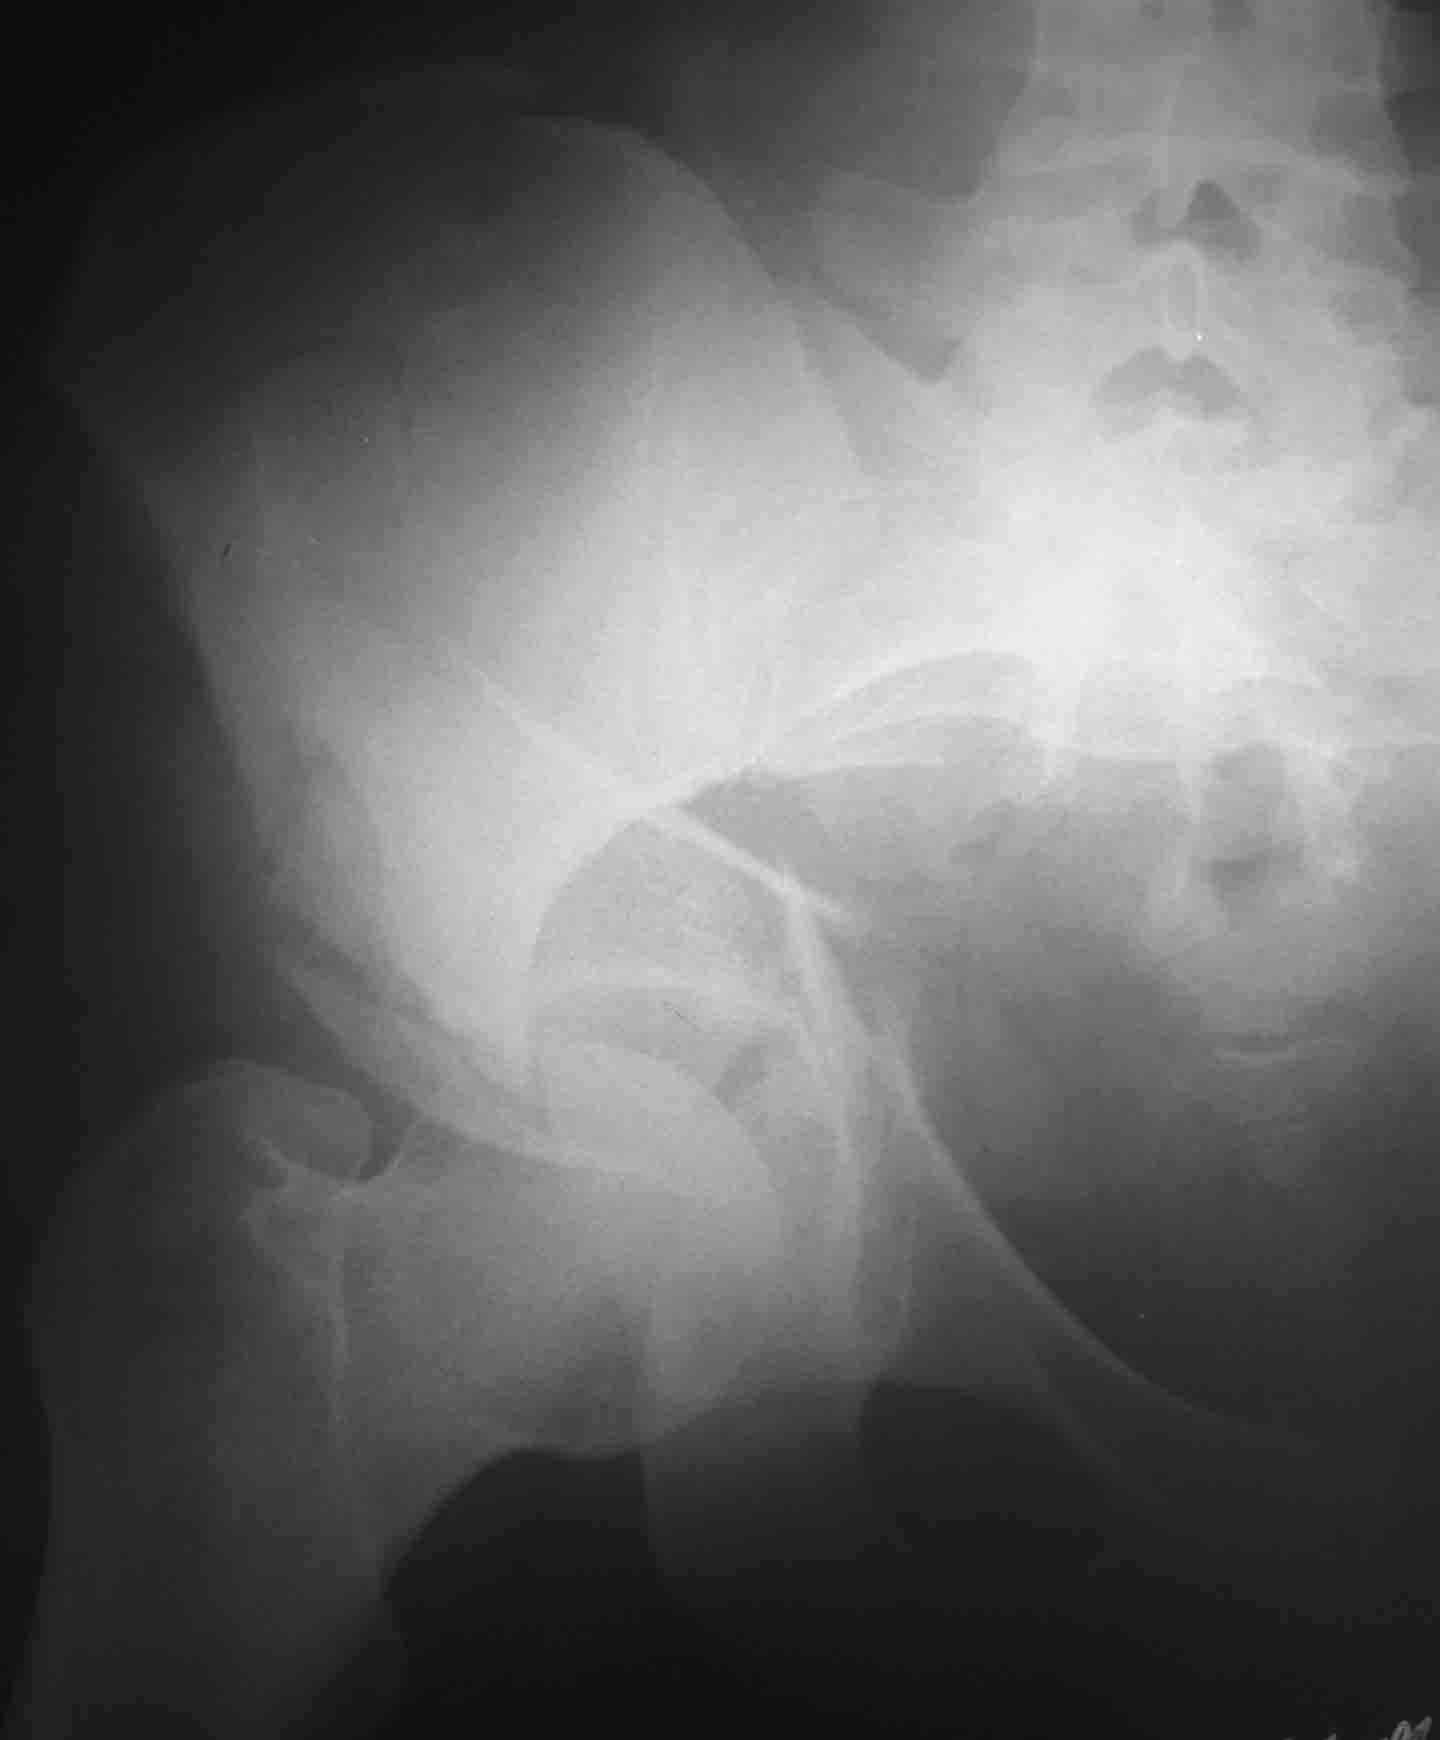

Пациентка 26 лет поступила в больницу 9 дней назад после кататравмы (падение с 4-го этажа)Тяжелая сочетанная травма: Ушиб головного мозга средней тяжести.З/полифокальный перелом таза (оскольчатый чрезвертлужный справа, латеральной массы крестца слева со смещением отломков. З/оскольчатый перелом н/3 правого бедра. З/оскольчатый перелом правой пяточной кости. Тупая травма живота - разрыв слизистой толст кишечника, кисты яичника.

Первым этапом штифтование бедра, лучше длинная Gamma, чко пяточной кости в максимально простой комплектацией (с пяткой можно будет разобраться позже, результат все равно будет "не очень", так что, скорее всего, дело закончится артродезом), вытяжение за мыщелки бедра 12-15 кг. Вторым этапом (максимально рано, насколько это возможно) внутренний остеосинтез вертлужной впадины (планирование и выполнение доступов можно посмотреть на http://odoc.ru/art_cont.php. Похоже, что вы имеете дело с низким двухколонным переломом, для уточнения необходимы проекции Judet.

Разве перелом крестца компрессионный, а расхождение, а вертикальное смещение?

И обратите внимание на подозрительную ступень на уровне левой подвздошной кости (перелом крыла с образованием треугольного фрагмента?).

Может это билатеральное повреждение таза, причем нестабильное с обеих сторон, + двухколонный перелом вертлужной впадины с задним краем?

1 ретроградный закрытый интрамедулярный синтез бедра (вертел труднодоступен и это зона последующих операций)

2 подвздошным доступом (положение на снине с вытяжением по оси бедер с двух сторон большими грузами 15-20кг) синтез подвздошной кости и передней колонны пластинами, илиосакральные винты справа

3 в положении на боку задне-наружным доступом синтез задней колонны и края.